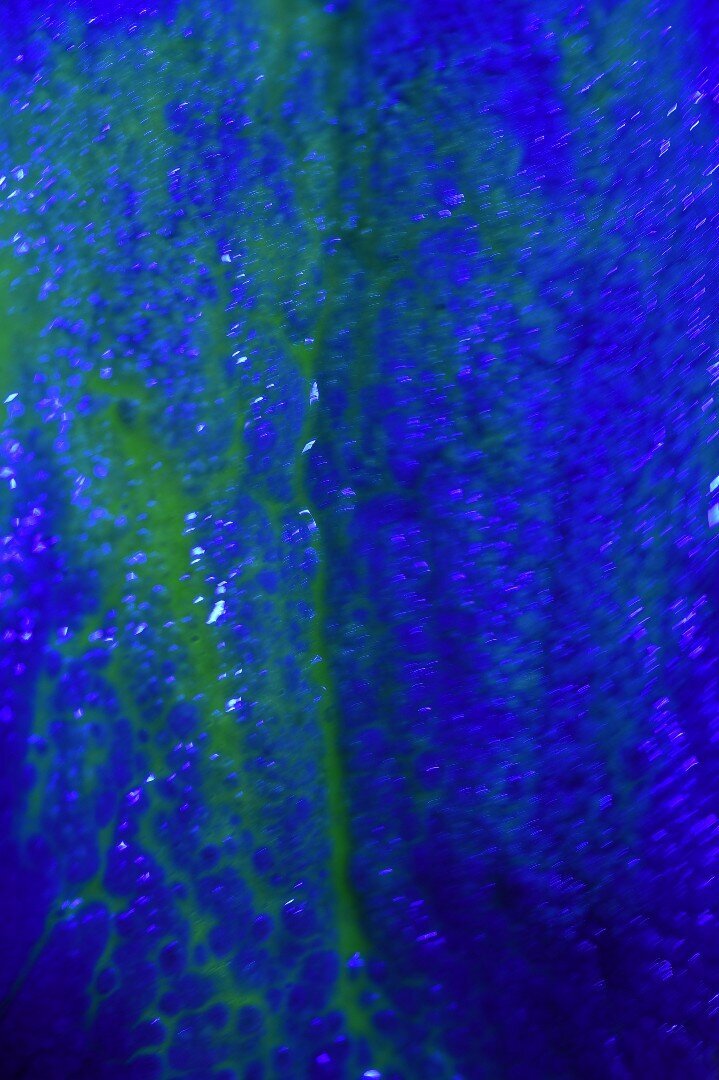

Vengono rilevati gli indici clinici e vengono condivise con il paziente le immagini raccolte con la videocamera intraorale, così da motivarlo di fronte alla presenza di tartaro e infiammazione gengivale e mostrargli le aree critiche. Viene apposto il rilevatore di placca alla fluorescina ed illuminato da una lampada fotopolimeralizzante, che permette di visualizzare la topografia del biofilm batterico (D-BIOTEK-TECNICHE)2, in modo da condividere con il paziente i siti più a rischio del cavo orale (Figg. 1a-2f).